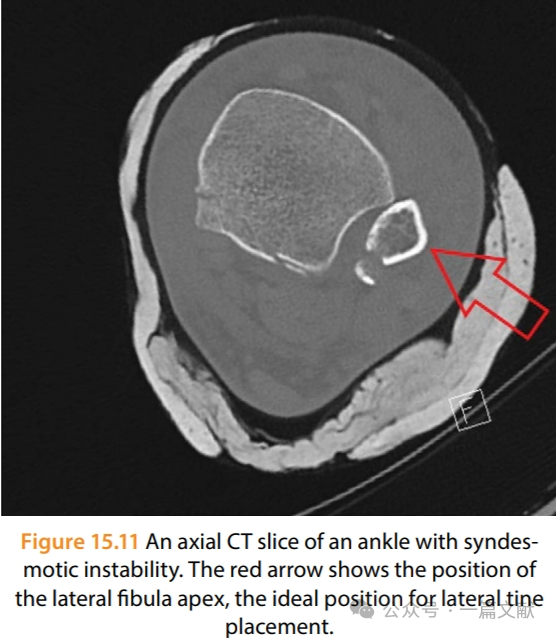

3,复位下胫腓时,复位钳夹持方向出现偏差,或螺钉置入方向有误,造成腓骨一定程度的旋转,未解剖复位。如下图:理想的夹持复位点是腓骨远端外侧凸起与内踝前部最高点,来实现踝关节的轴向加压。螺钉置入时同理。建议前方直视下观察腓骨远端与胫骨切迹的关系。